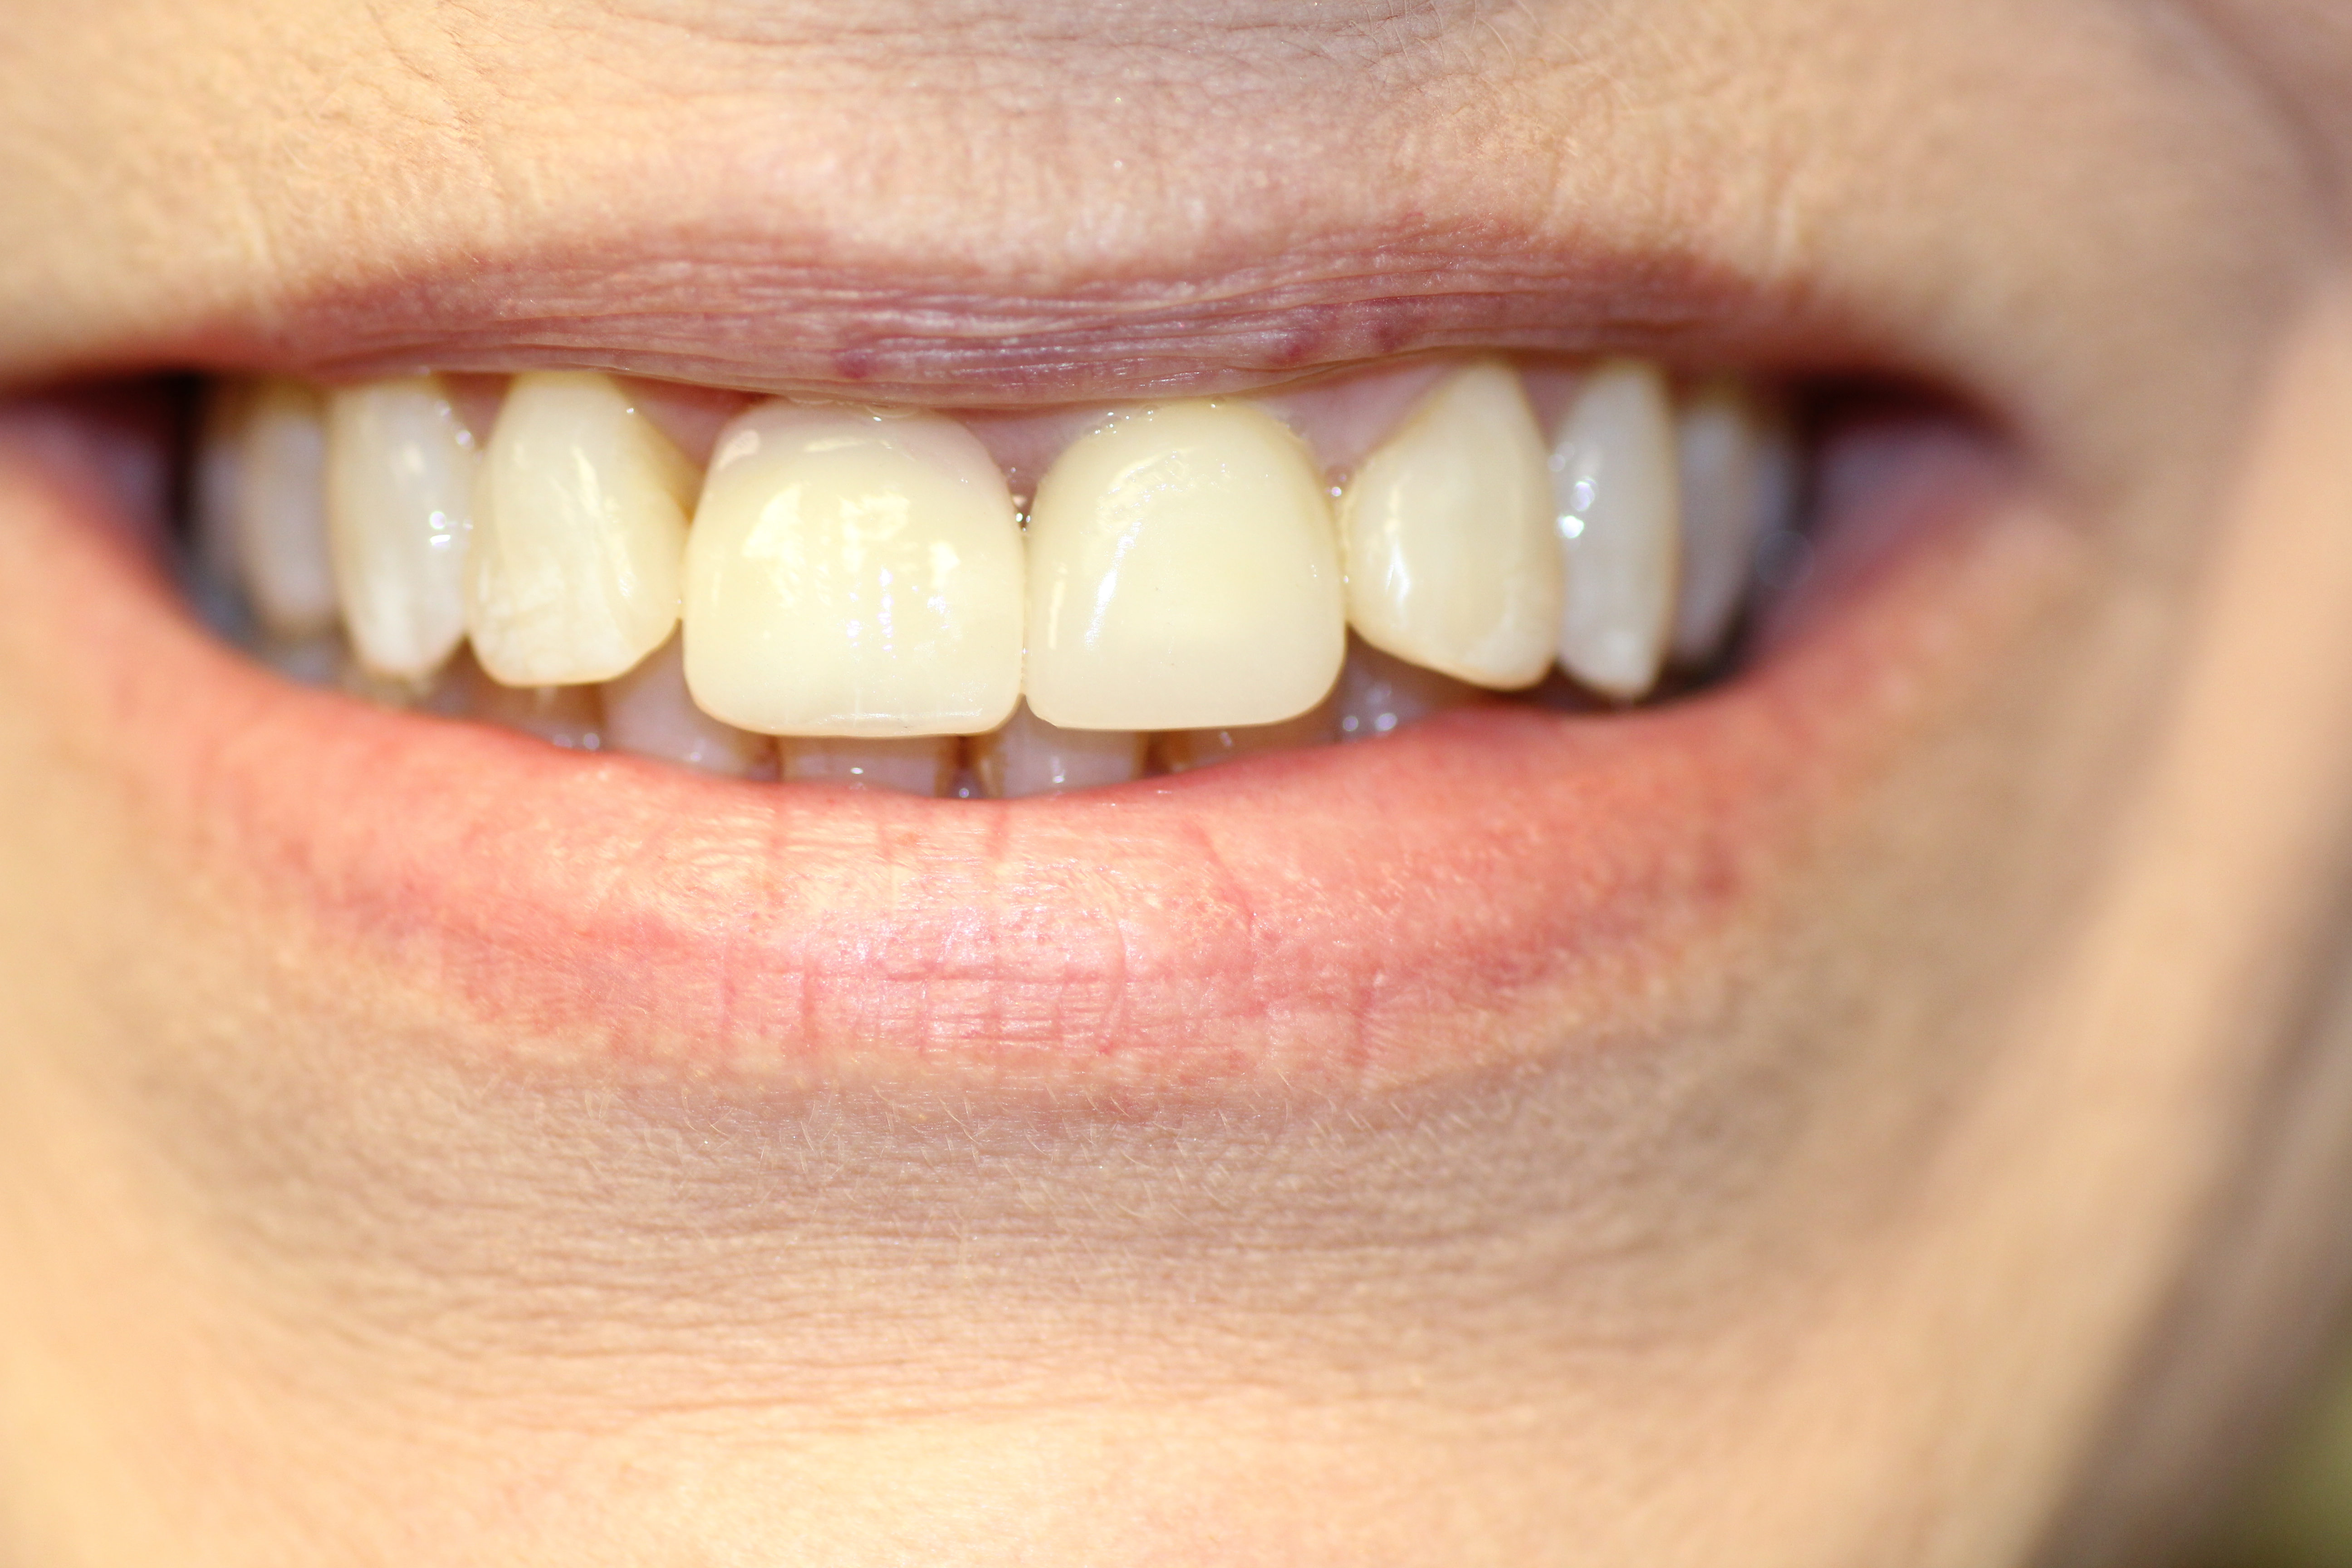

- Here shown is the patient with her implant smiling after the implant treatment.